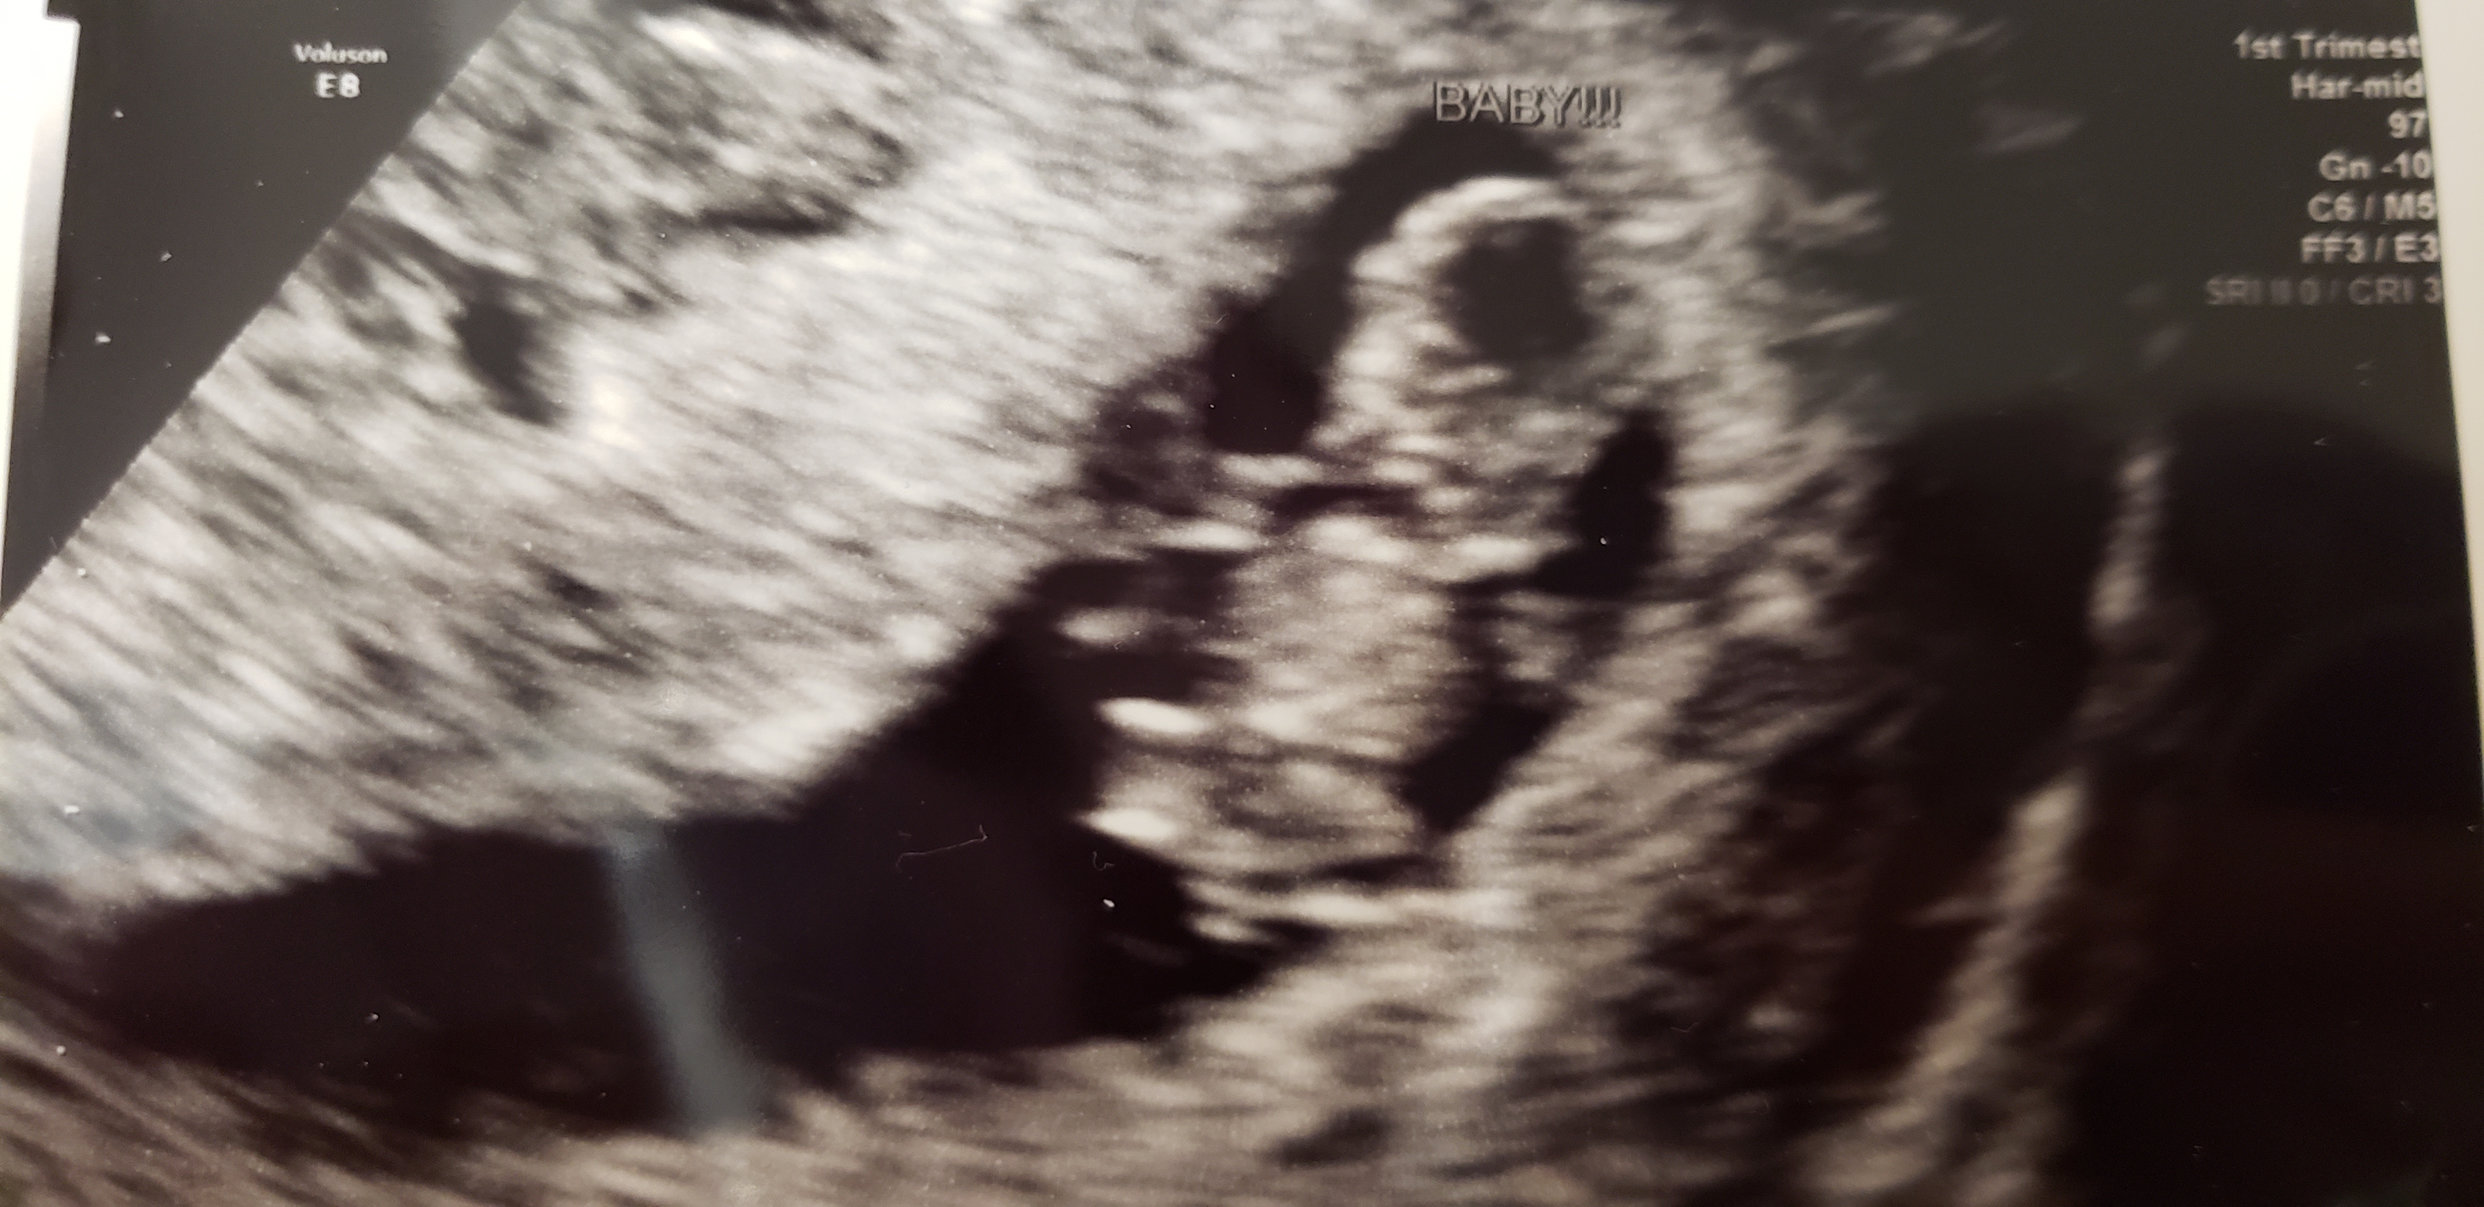

• First US on Monday, measurements have me at 10 weeks today. About a week earlier than I thought. Heartbeat was awesome to hear 😊💗. Tech did a 4D as an experiment 😁.  In love with that chubby little face already💕💕.